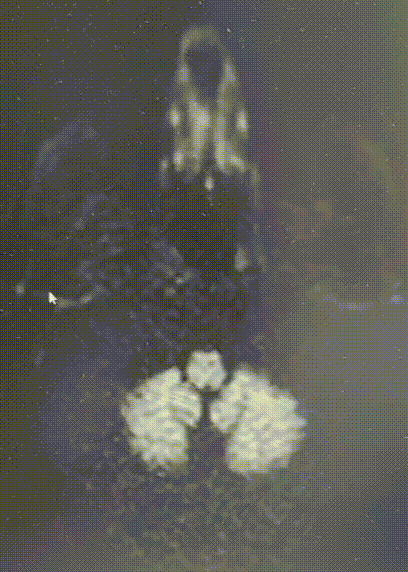

CTA

什么叫桡鞘畅疗·第十五期|畅医达 5F 0.072

2. 右侧颈内动脉起始段重度狭窄